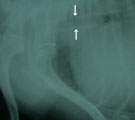

受診時。重度の呼吸困難。首を伸ばして両前足を立てている。 ステント設置前。胸部気管が扁平化。左には気管チューブがみえる。 ステント設置3日後。胸部気管がステントにて開大している。 6日後。呼吸は安静となり、じっと立てるようにはなった。この日に退院。

経過:8月初旬の猛暑時に来院。受診時、体温40.3℃。パンティングとチアノーゼを示す喘鳴症状がみられた。ただちに流水で体を冷やし30分後に35.8℃まで体温が下がったが、喘鳴・呼吸困難症状が続いた。心疾患の既往はなく気管虚脱が疑われた。酸素室中でも呼吸困難を示した。緊急にシリコンチューブにて気道拡張用ステントを作成し、100%酸素吸入全身麻酔下においてステント挿入による気管拡張術を行った。透視下にて胸部気管の扁平化を確認しその部位にステントを設置した。その後、気管支鏡でステント後方の気道に問題ないことを確認した。翌日、呼吸は安静化し夕方には自分で食事を食べるようになった。しかし体を動かすと喘鳴が始まった。6日後には立っても呼吸が安静でいられるようになり退院となった。